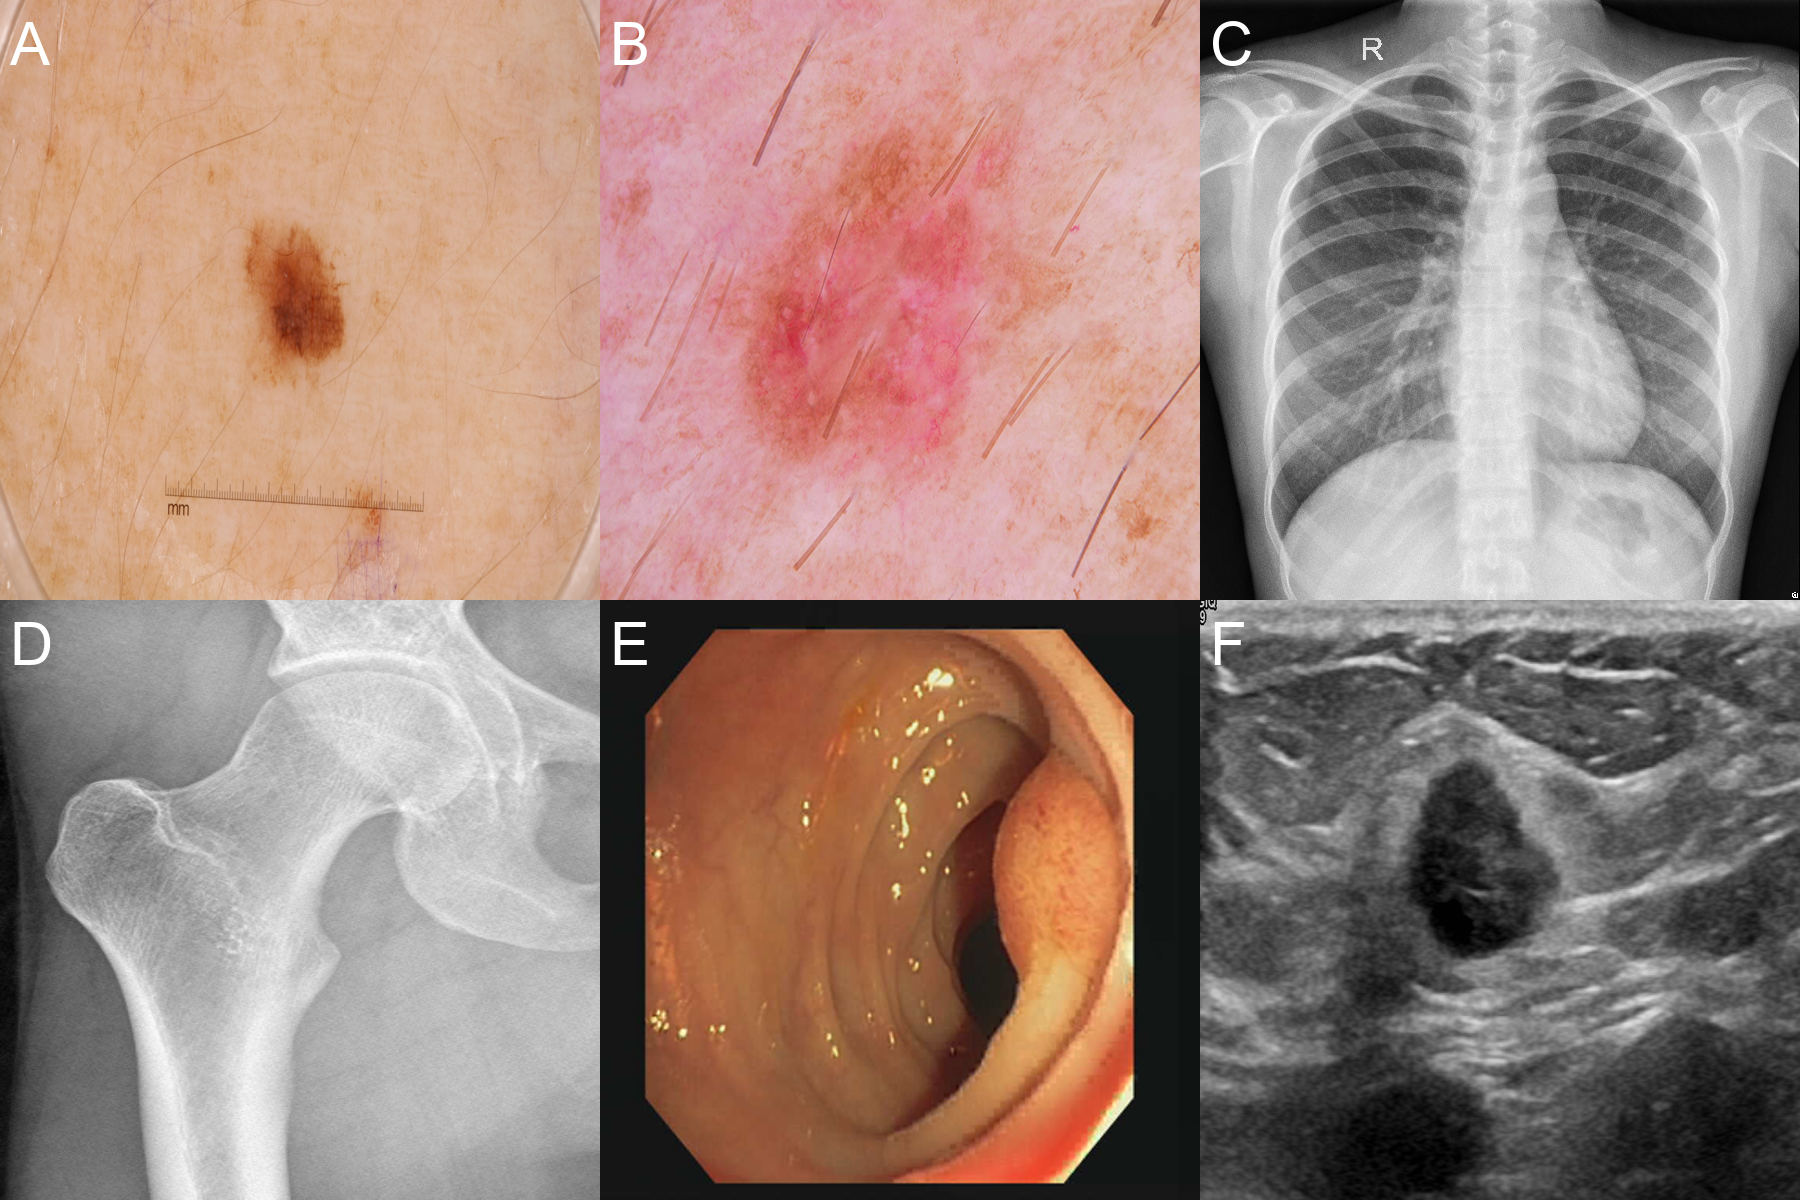

For evaluating SAM, we used six datasets from four medical imaging modalities: X-ray, Ultrasound, dermatoscopic, and colonoscopy images. Our primary objective is to assess the model’s performance and versatility when prompted with various strategies, simulating a physician’s approach to segmenting specific organs or ROIs in medical images. Fig 1 shows a sample from each dataset.

Refer to caption

Figure 1: Samples from each of the six datasets used in this study. A: ISIC, B: HAM, C: CXR, D: HJXR, E: CVC, F: BUSI.